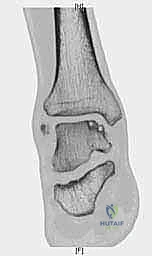

لفهم أهمية وصعوبة هذه الجراحة، من الضروري والمهم جداً أن نلقي نظرة طبية دقيقة على تشريح الكاحل. الكاحل ليس مجرد مفصل بسيط، بل هو تحفة هندسية حيوية، مفصل معقد يتحمل وزن الجسم كاملاً بالإضافة إلى قوى مضاعفة أثناء الأنشطة الرياضية. يتكون مفصل الكاحل من التقاء ثلاثة عظام رئيسية:

عظم الكاحل (التالوس): حجر الزاوية

عظم الكاحل هو عظم فريد من نوعه في جسم الإنسان. يتميز بأن الغضروف المفصلي يغطي حوالي 60% إلى 70% من مساحة سطحه الكلية. لا توجد أوتار أو عضلات تلتصق به مباشرة، بل يعتمد بالكامل على الأربطة لتثبيته. إنه بمثابة "حجر الزاوية" في قبو مفصل الكاحل، حيث يتمفصل من الأعلى مع عظم الظنبوب لتكوين المفصل الظنبوبي الكاحلي (Tibiotalar joint)، ومن الداخل مع الكعب الإنسي (Medial Malleolus)، ومن الخارج مع الكعب الوحشي (Lateral Malleolus). هذه الترتيبات الهندسية المعقدة هي التي تسمح بحركة الانثناء الأخمصي والانثناء الظهري (رفع وخفض القدم) الضرورية للمشي والجري.